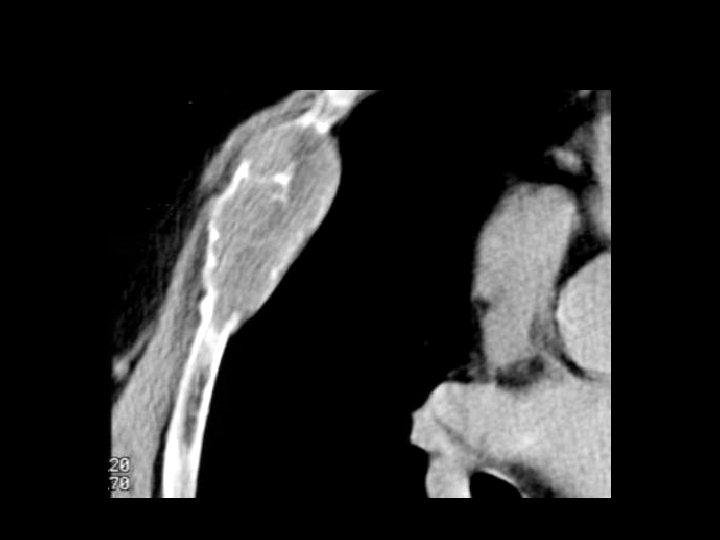

Lymphoma • Findings: – Permeative lytic lesion of the humeral diaphysis – Periosteal reaction and soft tissue swelling • ddx: – Osteomyelitis – Metastasis – Ewing’s Sarcoma – EG